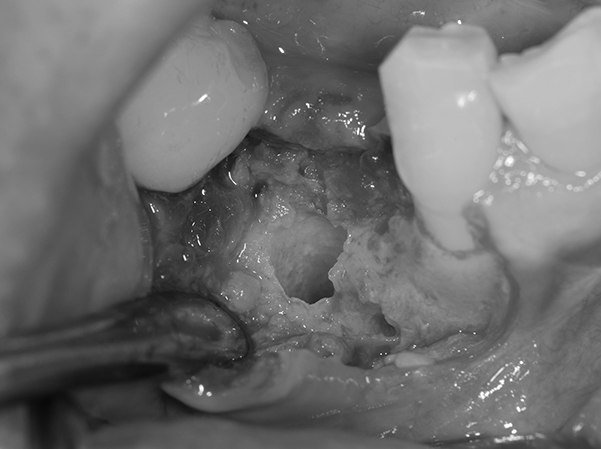

そのため、骨をてっぺんと穴の空いた部分に作る。 そのために、人工の骨をおき、チタンのメッシュで固定する。 この状態で6ヶ月ほど待機する。

麻布十番歯科のインプラント治療で人工の骨をおき、チタンのメッシュで固定している症例写真

6ヶ月後再び歯茎を切り中の状態を確認。骨がしっかりできており、インプラント手術を行えることが分かると思う。 インプラントを埋めるための穴をあけて、インプラントを埋入した。